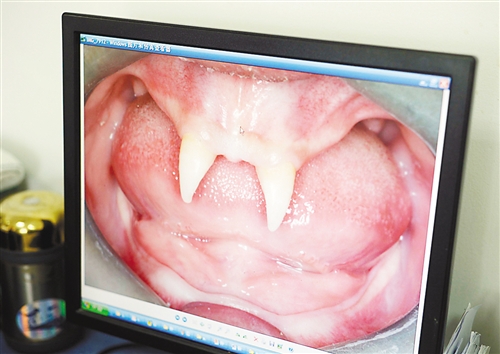

12月18日,16歲的張成(化名)從小到大,只有上顎部分有兩顆牙,看上去更像長著一對獠牙。 記者熊明攝

張成是貴州銅仁地區思南縣人,從生下來就似乎得了一種怪病,身上毛發稀少,面部發育也不好。更奇怪的是,別人家的孩子都長牙吃東西了,他卻一直長不出牙齒,最后只在上顎部分冒出兩顆比較突出且對稱的牙齒,看起來就像一對獠牙。